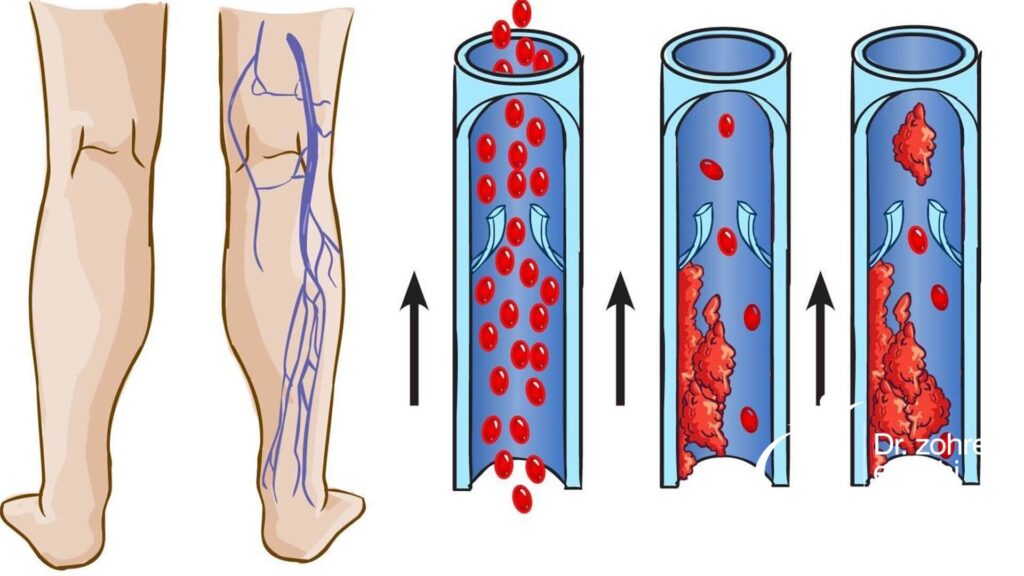

انواع درد عصبی ساق پا

سیاتیک و تنگی کانال نخاعی

آرتروز ستون فقرات یکی از علل شایع تنگی کانال نخاعی است.

گاهی اوقات، فتق دیسک با وارد کردن فشار زیادی بر روی ریشههای عصبی، علائم کمردرد و سیاتیک را ایجاد می کند، مانند خستگی، ضعف، بیحسی، گزگز و درد پایین پاها (پشت و/یا کنار ساق پا) هنگام نشستن یا ایستادن.

با تنگی کانال نخاعی احتمال آسیب به عصب فمورال نیز وجود دارد که منجر به درد ساق پا در قسمت جلویی ساق پا خواهد شد.

نوروپاتی محیطی

آسیب به اعصاب محیطی در اندام ها می تواند باعث بدن درد شود. این بیماری در میان افراد مبتلا به دیابت و مصرف کنندگان برخی داروها شایع است.

آسیب موضعی عصب

به غیر از آسیب های عصبی متمرکزتر، احتمال آسیب موضعی اعصاب پایین ساق نیز وجود دارد.

این آسیب اغلب همراه با یک جراحت دیگر اتفاق میافتد، به طوری که التهاب موضعی ناشی از جراحت، باعث فشردگی یا گیرافتادگی عصب شده و منجر به درد ساق پا میشود.